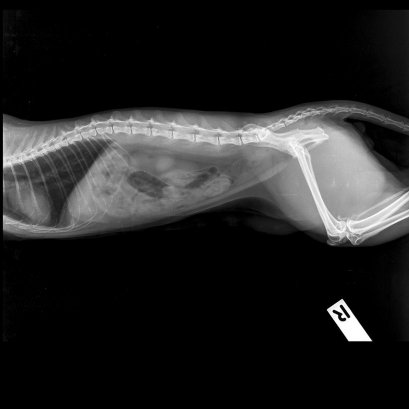

CAT

น้องโทโทโร่ เป็นน้องแมวพันธุ์ Exotic Shorthair อายุประมาณ 9 เดือน เข้ามาตรวจกับแผนกอายุรกรรมเนื่องจากเจ้าของพบว่าน้องมีแผลที่ริมฝีปากด้านบนเกิดขึ้นได้ประมาณ 2-3 วัน